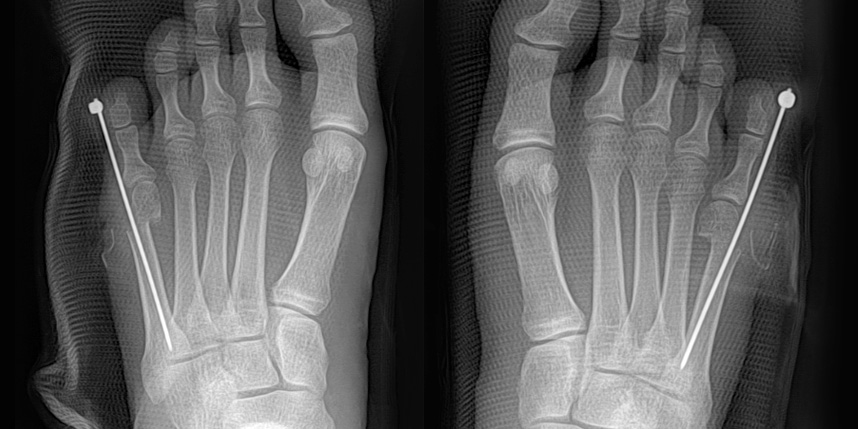

작은 구멍을 통해 초음파 절골기를 이용하여 뼈를 절골합니다.

중등도 이상의 큰 각도의 소건막류에도 충분히 적용이 가능합니다.

빨간 포탈을 이용하여 초음파 절골기를 삽입하여 절골을 하고 핀을 삽입합니다.

핀은 바깥으로 빼어 놓고, 6-8주째 외래에서 간단하게 제거합니다.